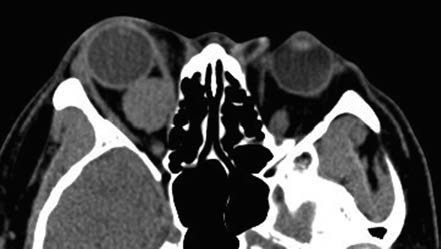

Figure 2 CT imaging of a right orbital cavernous venous malformation

A triangular hypodense area of orbital fat is visible at the orbital apex.

On CT imaging, cavernous venous malformations typically appear well-demarcated and homogeneous in density. Signs such as optic nerve compression, displacement, and orbital cavity enlargement can be observed. CT imaging can also assess the degree of lesion adhesion. When fat is present at the posterior margin of the lesion, a triangular area of hypodense orbital fat is visible at the orbital apex on CT, suggesting minimal adhesion to surrounding tissues. Cavernous venous malformations without this hypodense orbital fat feature often exhibit significant adhesion. MRI findings show iso-intensity on T1-weighted images and hyperintensity on T2-weighted images. The hallmark of dynamic contrast-enhanced imaging is progressive enhancement, where small areas display early patchy enhancement that gradually becomes diffusely and homogeneously enhanced over time.